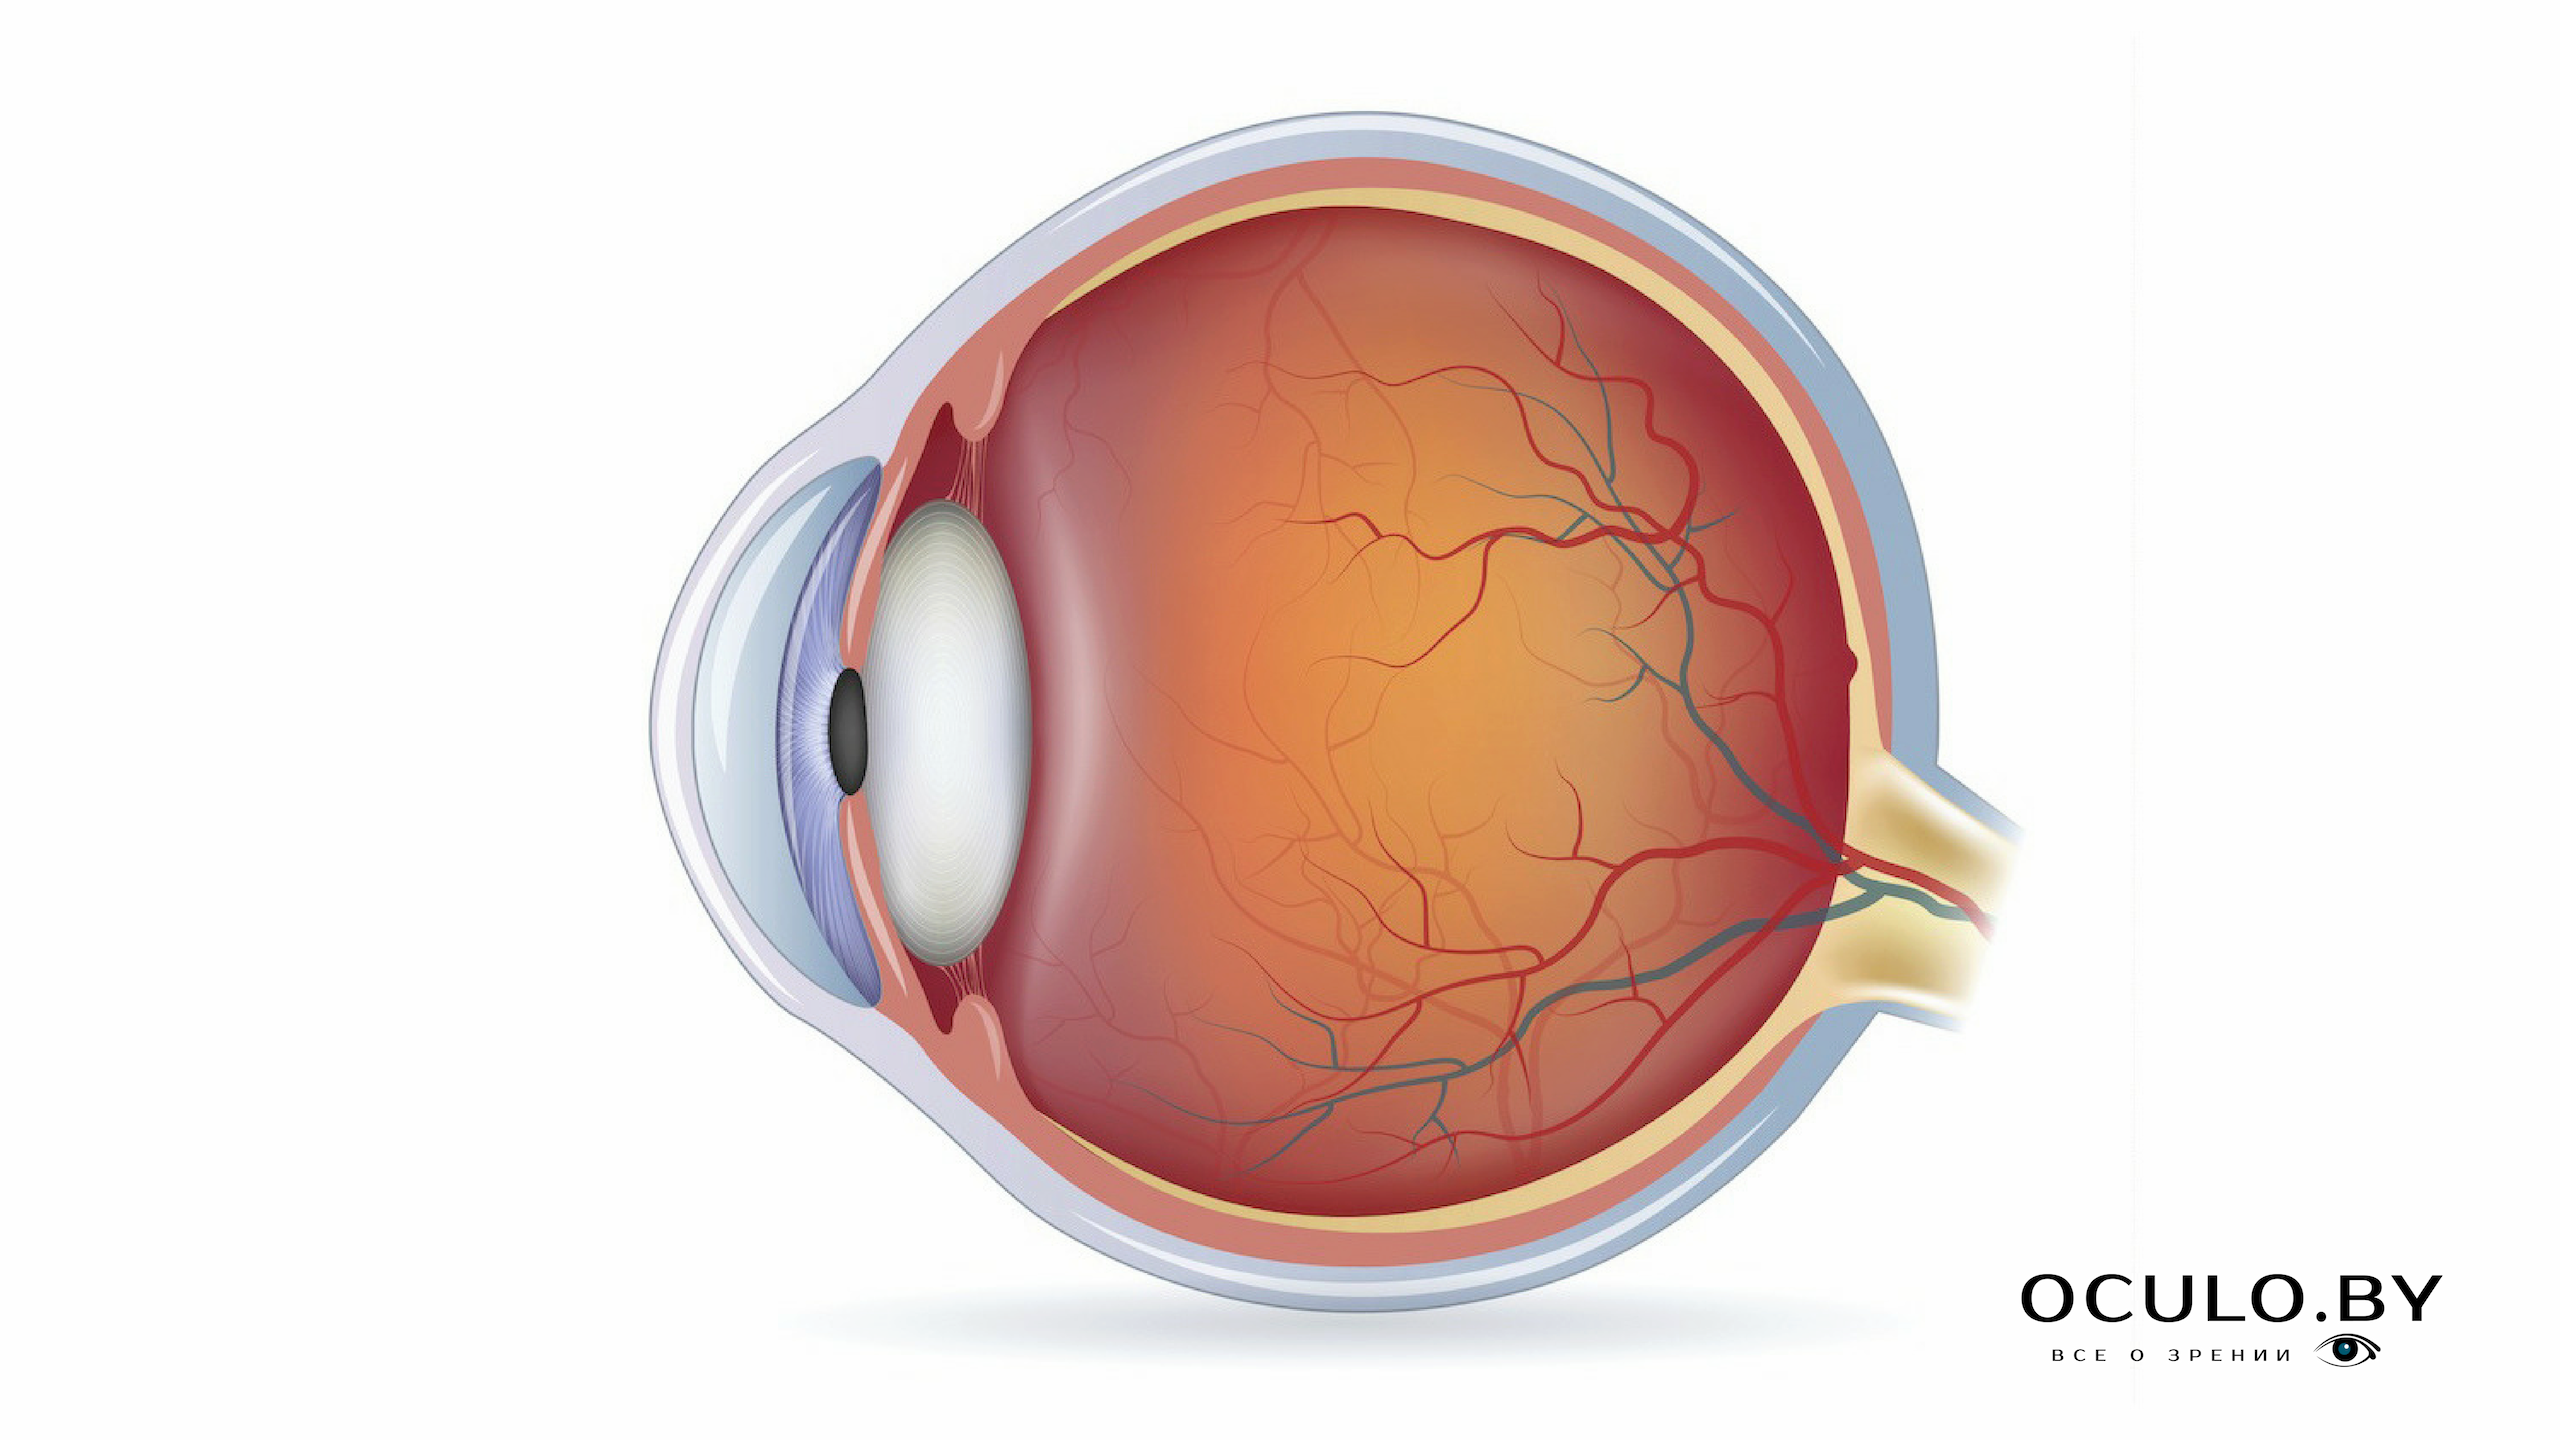

Изображения и анатомия сетчатки глаза

Раздел: Визуальный дайджест